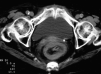

Fig. 1. Cortes axiales consecutivos de tomografía computarizada (TC) abdominal donde se aprecia la invaginación intestinal y un mioma uterino calcificado (A).